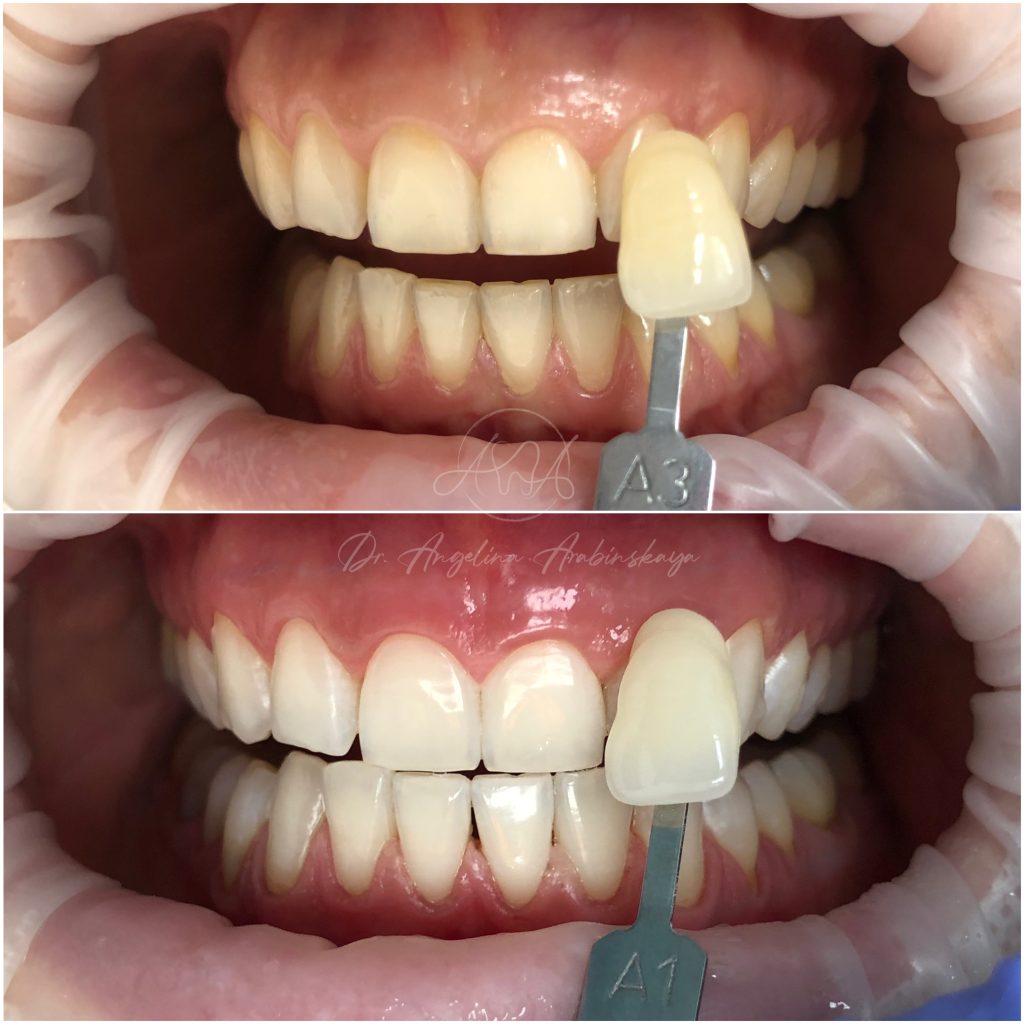

• Профессиональная отбелка зубов системой ZOOM,BEYOND

• Домашнее отбеливание зубов

2024 год – «Отбеливание от «А» до «Я» Александр Кирманов